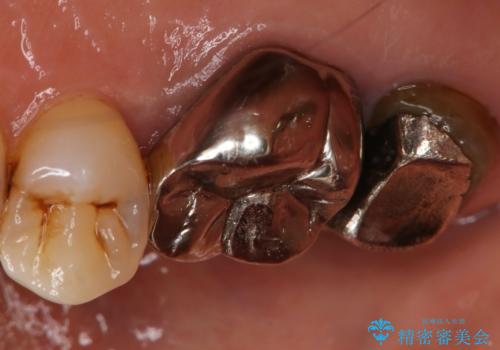

- 右上大臼歯の被せ物が取れたので作り直しを希望された患者様です。

被せ物は白くしたいとのことだったのでフルジルコニアクラウンでの治療を選択しました。

根管治療も必要だったので金属の土台を除去し、新しく土台を立て直した上で被せ物を装着しています。